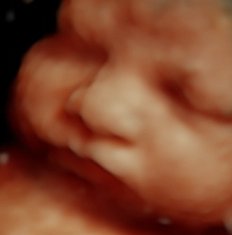

Com a inovação da medicina diagnóstica a ultrassonografia em 4D consegue avaliar a morfologia fetal em três dimensões em tempo real. As imagens tridimensionais permitem ver estruturas como as mãos, pés, orelhas, nariz, boca e ainda a fisionomia do bebê.

A Imax possui o mais novo aparelho de ultrassonografia obstétrica o Voluson E8 Expert HD Live, o qual permite um diagnóstico mais confiável através da visualização de imagens fetais com alto realismo anatômico.